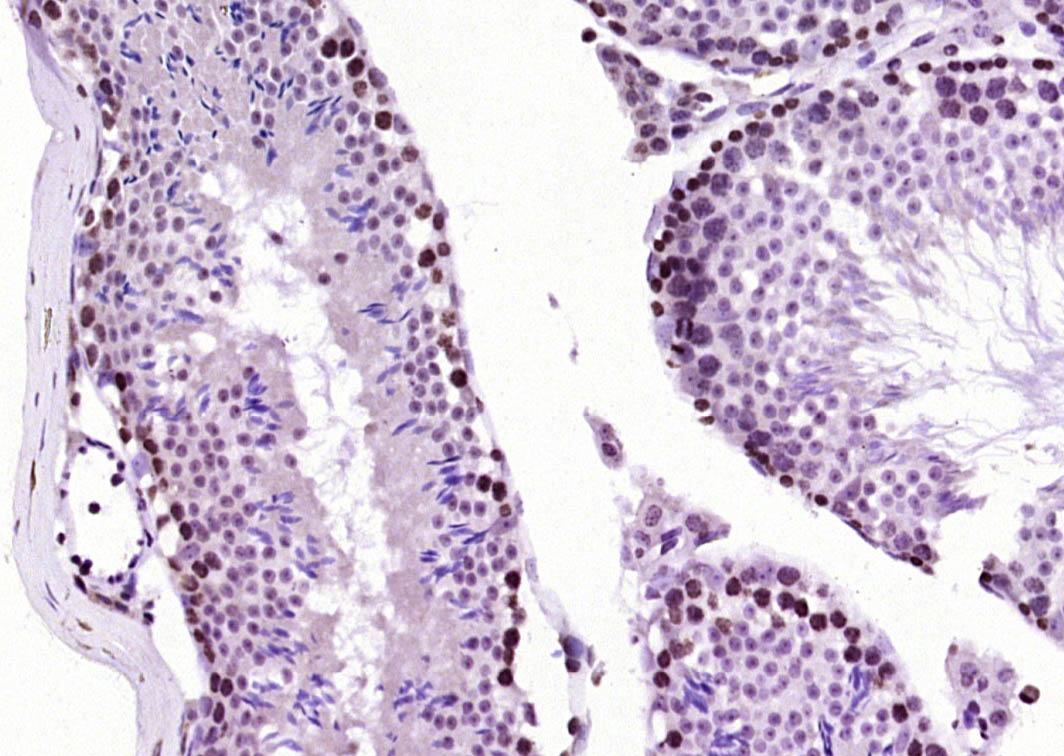

Antigen retrieval: citrate buffer ( 0.01M, pH 6.0 ), Boiling bathing for 15min; Block endogenous peroxidase by 3% Hydrogen peroxide for 30min; Blocking buffer (normal goat serum,C-0005) at 37℃ for 20 min;

Incubation: Anti-CIRBP Polyclonal Antibody, Unconjugated(bs-7790R) 1:200, overnight at 4°C, followed by conjugation to the secondary antibody(SP-0023) and DAB(C-0010) staining